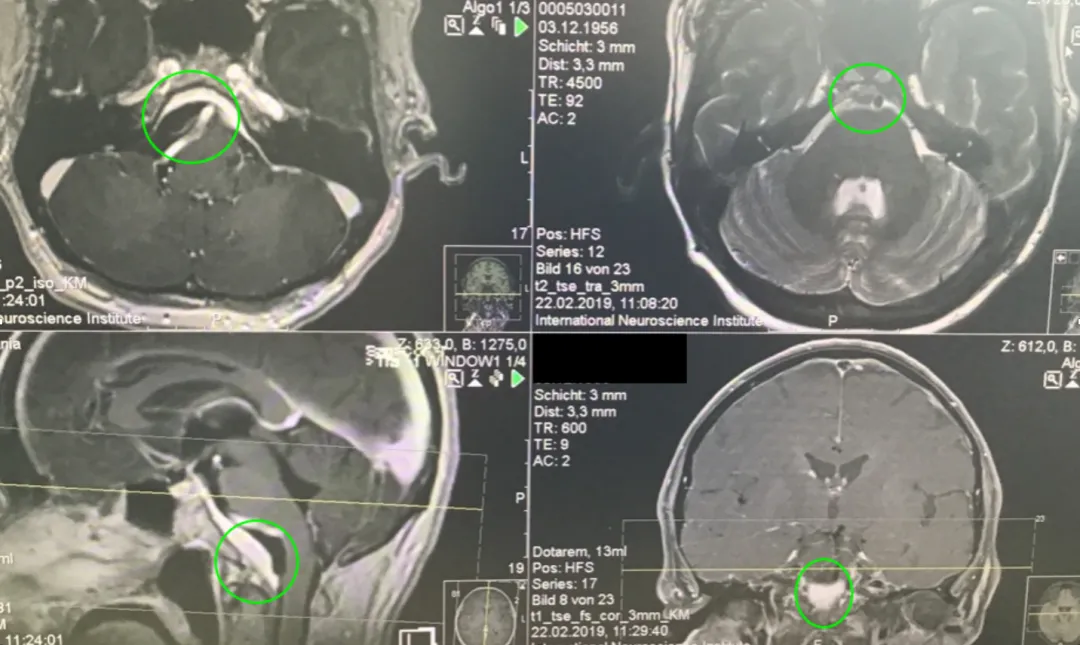

一名40余岁女性患者持续一年多的症状进行性加重,相继出现头痛、复视、肢体无力和吞咽困难等表现。当地医院诊断为岩斜区巨大脑膜瘤,辗转多家医疗机构均被告知手术风险较高、术后并发症发生率高。后寻求INC巴特朗菲教授手术治疗,实现肿瘤近全切,未出现相关手术并发症。

术后MRI证实:肿瘤近全切除,未见脑血肿或脑水肿,神经血管和脑干组织保护完好